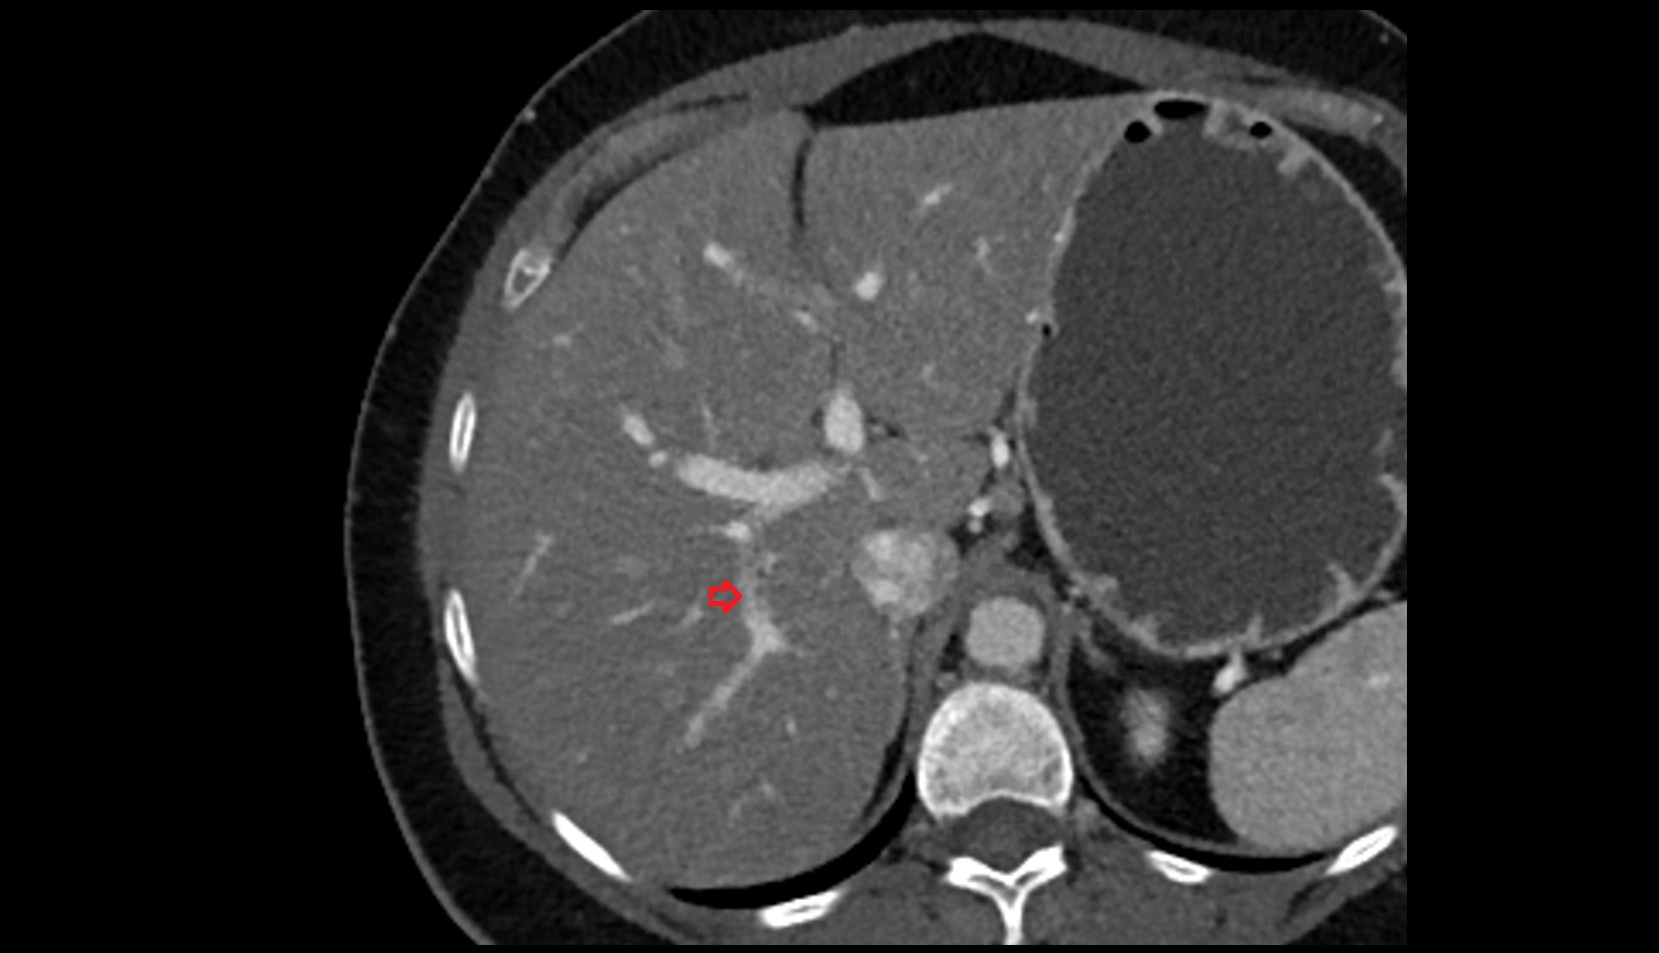

- Right lobe of liver

- Liver